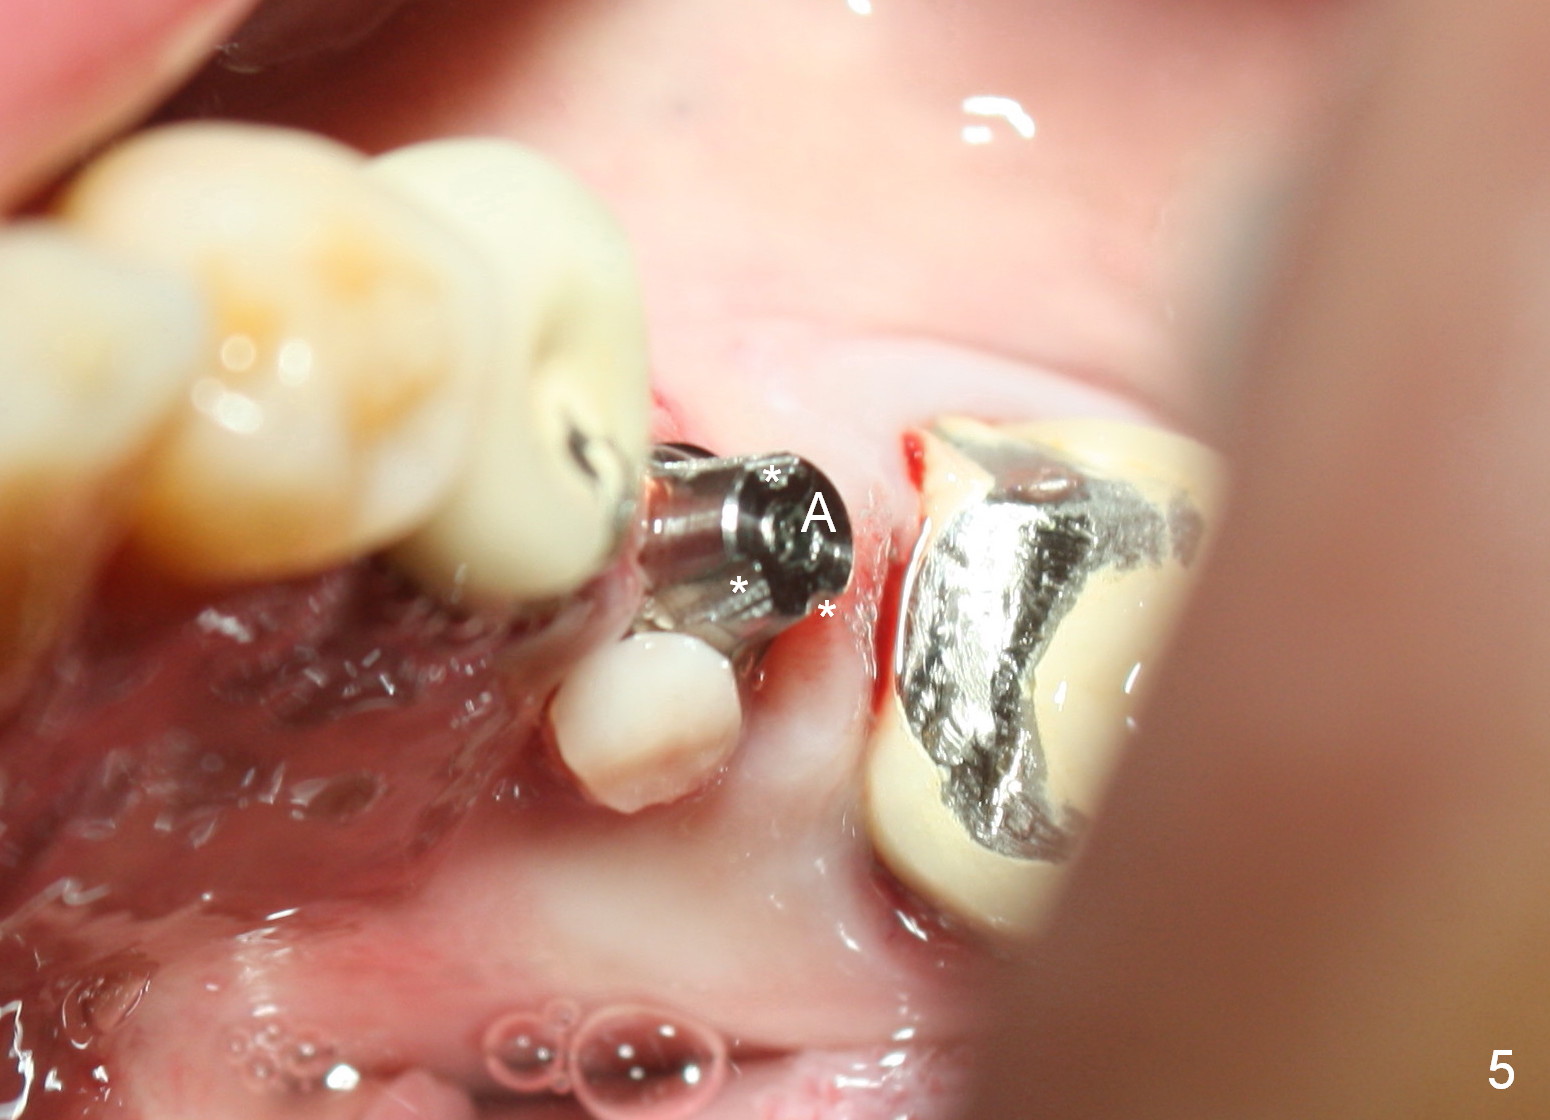

A 47-year-old man has history of bruxism, chipping porcelain from #29-31 FPD (Fig.1). Following sectioning the FPD, osteotomy is created (Fig.2: 5x14 mm drill) for placement of a 5x14 mm tissue-level implant (Fig.3,4). A 4x3 mm abutment (Fig.5 (lingual view) A) with 3 vertical slots (* for increased retention) is placed to retain periodontal dressing. The crown over the implant has dislodged 3 times over 28 months post cementation (Fig.6). It appears that the top of the abutment is too rounded. Clinical exam shows that the abutment height can be more, although the tooth #3 is supraerupted (Fig.7 (orthodontic intrusion is not indicated because of furca infection)).

Pre-impression photos show supraerupted #3 (Fig.7). Clearance is a little more than 1 mm between the mesiopalatal cusp of #3 (Fig.7 *) and the rounded abutment (Fig.8). Removal of the abutment turns out to be easy. Reduction is confined to the opposing tooth (slopes of the cusps). No occlusal reduction is done for the new abutment as mentioned above except for 2 retention grooves. One-mm reduction ring barely passes the occlusal clearance (Fig.9). No cement is applied to the abutment in case a longer abutment may be required. Bone density seems to remain the same or increase after cementation of a new crown (Fig.7). The redo crown remains in place 1 year post cementation.